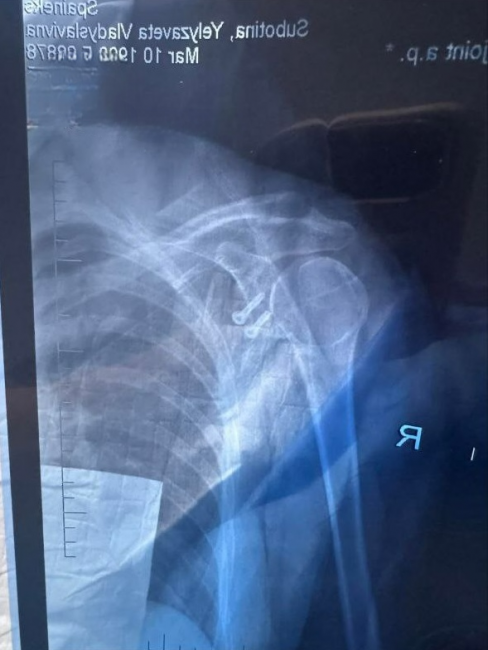

Лізу доправили до травматології. Медики встановили вивих плеча та розрив плечової губи — тканини, яка утримує суглоб. Після МРТ з’ясувалося, що є кістковий дефект суглобової поверхні лопатки, а отже — показання до оперативного втручання.

Йшлося про стабілізацію плечового суглоба за методом Латерже — під час цієї операції частину дзьобоподібного відростка лопатки переносять на суглобову поверхню, щоб збільшити її площу та запобігти повторним вивихам. Простішими словами — частину кістки перемістили та зафіксували гвинтами. Розріз становив близько 6–8 сантиметрів.

10 лютого Лізі провели операцію у вінницькому медичному центрі «Spinex». Оперував Вадим Луцишин, другим хірургом був Андрій Конюк, який і проводив первинну діагностику. Втручання тривало близько двох годин.